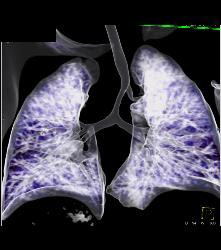

Right Tracheal Bronchus and Tracheal Stenosis in Trachea Below Right Tracheal Bronchus- See Full Sequence